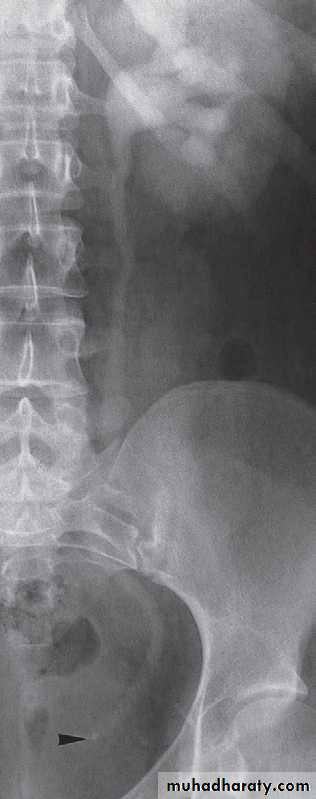

mainly replaced by CT scan & CT urography in patients with suspected acute obstruction, which is usually caused by a calculus.-In Plain films may demonstrate the calculus responsible for the obstruction .

-Following injection of intravenous contrast medium, a film of the renal tract is taken at approximately 15 minutes. If the urogram is normal, with contrast seen in normal, undistended ureters bilaterally,then this effectively rules out ureteric colic as the cause of acute pain.

-If one of the ureters is obstructed, then adense nephrogram will be seen and opacification of the pelvicaliceal system and ureter on the obstructed side takes much longer. Delayed films are, therefore, essential part of any IVU.